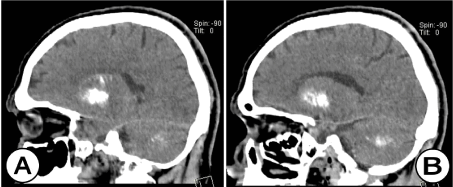

Рис. 6. Нативная КТ головного мозга (сагиттальная плоскость) (А) и (В): участки  кальцификации с вовлечением зубчатых ядер и гемисфер мозжечка, а также  базальных ганглиев (хвостатое ядро, бледный шар, чечевицеобразное ядро ​​и скорлупа) у того же пациента.